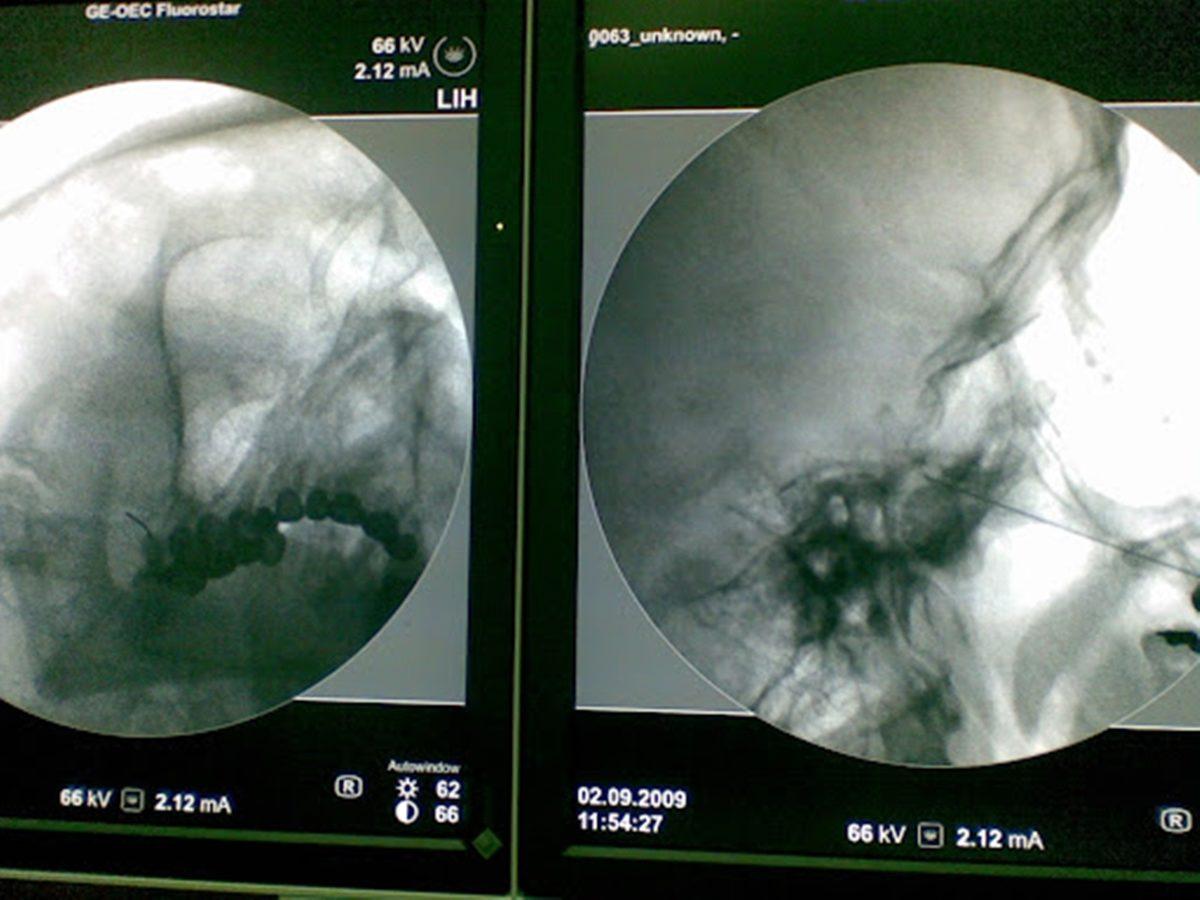

- Fotoğraf 1: Ağrıları yüzünden 32 dişini çektirmek zorunda kalan ve ötanazi isteyen hasta, başarılı bir operasyonun ardından eski sağlığına kavuşmuştu.

- Fotoğraf 2: Ağrıları yüzünden 6 dişini çektirmek zorunda kalan, 18 yıl sonra doğru teşhis konulan hasta, operasyonun ardından ağrılarından kurtulmuştu.